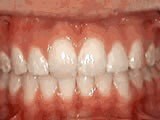

At age ten, patient had a big overjet with the top teeth protruding beyond the bottom. She had two phases of treatment. The first helped her jaws to grow more harmoniously and the second aligned her teeth and bite. At age 13, she was proudly displaying her new smile.